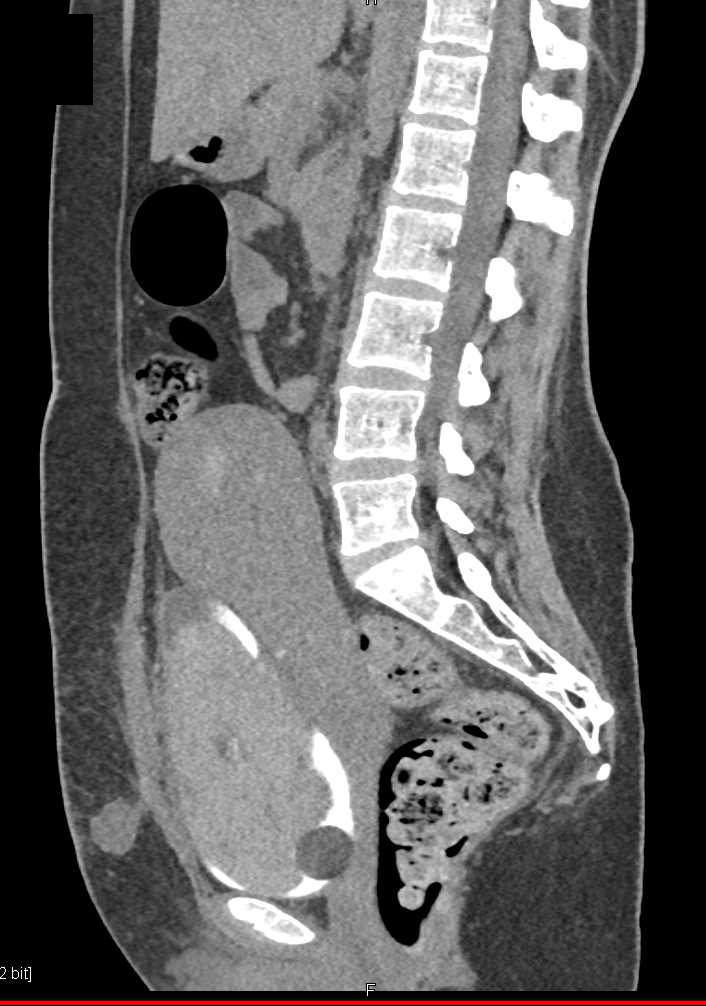

CCTA: Anomalous Origin of the Right Coronary Artery off the Pulmonary Artery (ARCAPA)